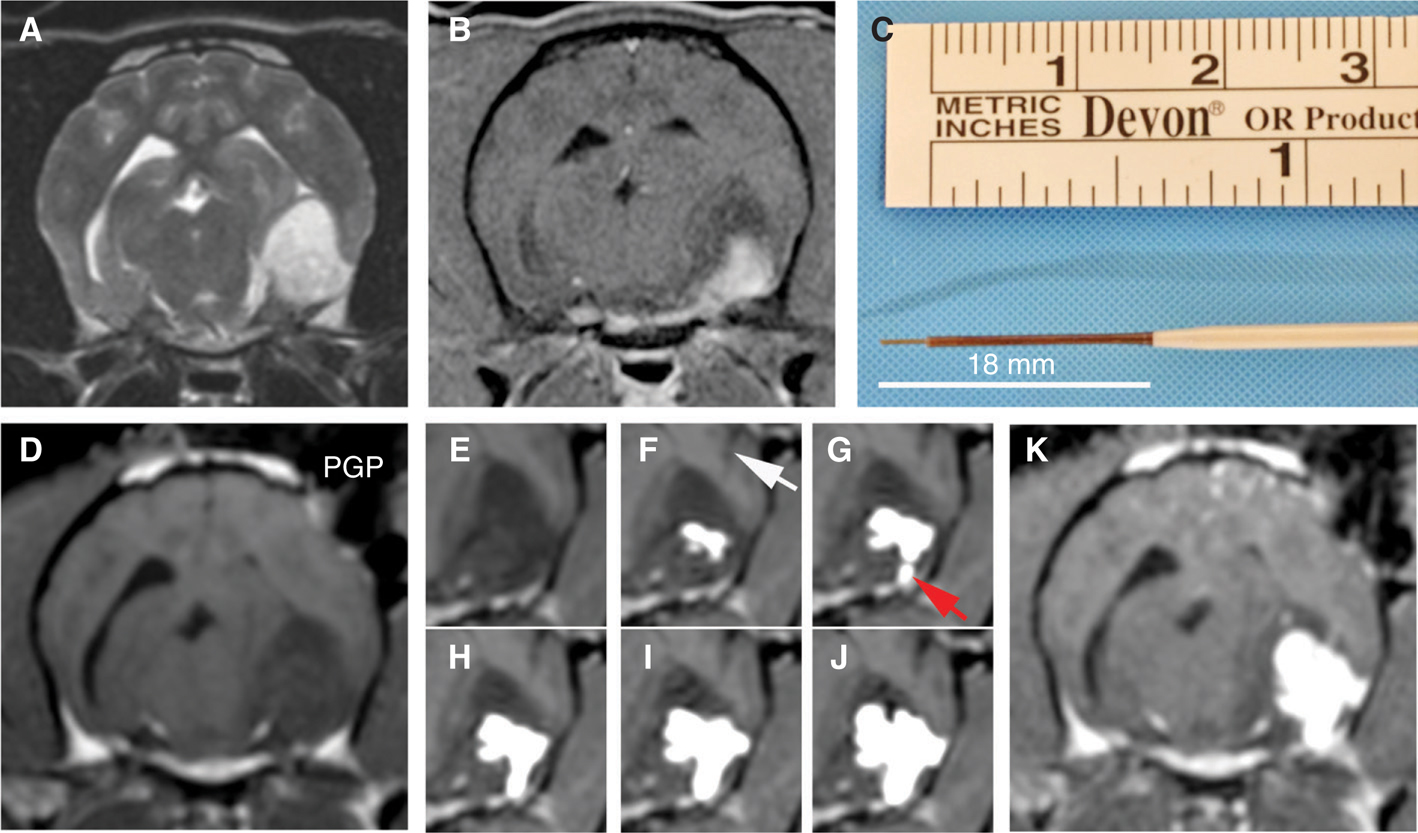

The histopathological and diagnostic imaging features of canine gliomas (Figure 1) are also remarkable similar to their human counterparts (31–35). These shared morphologic features facilitate comparative classification and grading of tumors using World Health Organization criteria (36) and performing objective imaging–based therapeutic response assessments using the Response Assessment in Neuro-Oncology (RANO) system criteria (28, 37). However, the frequency of glioma subtypes encountered in dogs differs from that seen in humans (Table 1), with oligodendrogliomas accounting for a significantly higher proportion of all canine gliomas compared to humans (19–21, 23, 37).

Figure 1 Comparative morphological and immunophenotypical features of human and canine glioblastoma (GBM). Post-contrast T1-weighted magnetic resonance images from a human (A) and dog (B) demonstrating ring-enhancing cerebral GBM. Classic microscopic features of hypercellularity and pseudopalisading necrosis in a human (C) and canine (E) GBM (H&E stain, bar = 150 μm). GBM from both species demonstrate intense immunoreactvity to IL-13RA2 (D, F).